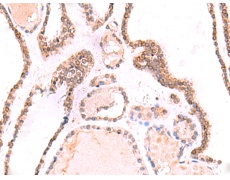

IHC positive control: |

Human thyroid cancer |

IHC Recommend dilution: |

50-300 |